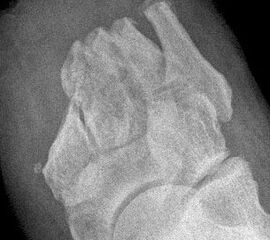

• angiopathischer Fuß:

• Ischämie von Anteilen der unteren Extremität, ohne dass eine Möglichkeit zur

• Revaskularisation besteht.

• Gewebeuntergang (Nekrose) ohne oder mit Infektion (Abb. 1)